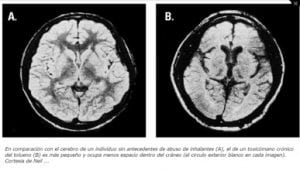

- Daño cerebral (pérdida de masa de tejido cerebral, trastornos cognitivos, trastornos de la marcha, pérdida de coordinación, pérdida de equilibrio, espasmos en las extremidades, pérdida auditiva y visual).